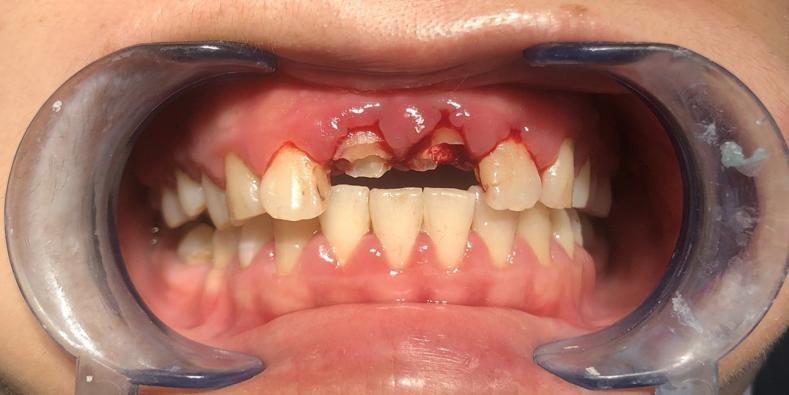

近日,广州市花都区人民医院口腔科通过规范的诊疗流程,为一名18岁男孩完成牙齿“蜕变”,让其重拾自信笑容。

这名男孩就诊时满口黑牙,颜值大打折扣。广州市花都区人民医院口腔科结合放射检查、内科治疗、外科干预及修复重建等诊疗环节,制定了“拍片检查—牙周治疗—拔牙—根管治疗—桩冠修复”的系统性方案,后续还将为其缺失牙进行种植修复。

根管治疗,树脂充填修复